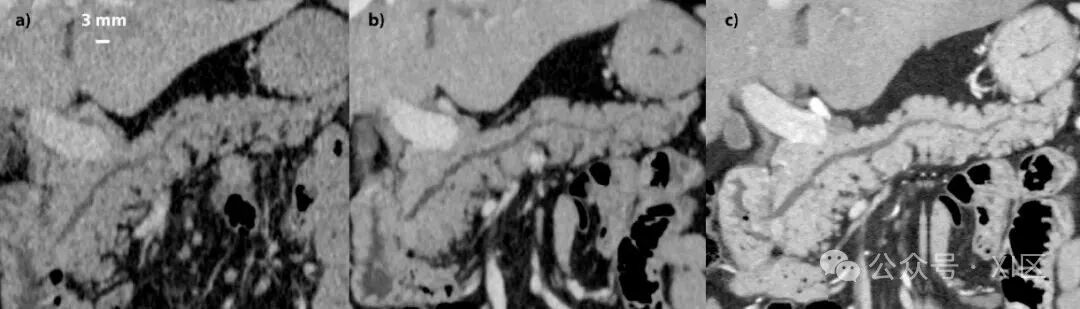

光子计数CT因其卓越的空间分辨率而非常适用于CT血管造影(A)。在本例中,肝细胞癌通过经动脉化疗栓塞术治疗,并且在手术过程中也进行了腹腔动脉造影(B)。CT血管造影充分地描绘了肝动脉至外周,这可以促进选择性导管插入到肝动脉分支中。

上图比较了传统CT和光子计数CT间图像质量的差异。(a) 来自采用双层光谱技术的门静脉期传统EID-CT(腹部CT的DLP为543)。(b) 来自门静脉期光子计数CT(整个胸部和腹部CT的DLP为720)。(c) 来自在动脉晚期(胰腺期)使用0.4毫米切片的光子计数CT(DLP为332)。